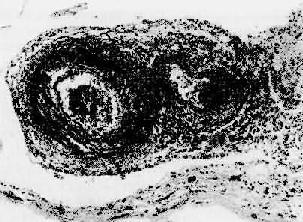

图4-12 红斑性狼疮之脾病变 脾小体中央细动脉壁呈洋葱皮样结构 (7)淋巴结:全身淋巴结均有不同程度的肿大,窦内皮增生。其中较多的浆细胞,小血管变化与脾所见相同。 2.口眼干燥综合征 口眼干燥综合症(Sjǒgren syndrome)临床上表现为眼干、口干等特征,乃唾液腺、泪腺受免疫损伤所致。本病可单独存在,也可与其他自身免疫病同时存在,后者最常见的是类风湿性关节炎、SLE等。病变主要累及唾液腺及泪腺,其他外分泌腺包括呼吸道、消化道腺体也可受累。 唾液腺的组织学病变主要表现为腺管周围大量炎细胞浸润,主要是淋巴细胞和浆细胞,有时可形成淋巴滤泡并有生发中心形成。伴腺管上皮增生,引起管腔阻塞。病变晚期腺泡萎缩、纤维化,为脂肪组织所替代。个别病例浸润的淋巴细胞形成淋巴瘤样结构。由于唾液腺的破坏而引起口腔粘膜干裂及溃疡形成。 泪腺的类似病变可导致角膜上皮干燥、炎症及溃疡形成。呼吸道、消化道受累可导致相应的鼻炎、喉炎、支气管炎、肺炎及萎缩性胃炎。在肾可发生间质性肾炎,肾小管周围大量单个核细胞浸润,导致肾小管萎缩、纤维化,因肾小管功能损害而引起肾小管性酸中毒、磷酸盐尿等颇常见。 淋巴结肿大并有增生性变化,核分裂多,故又名假性淋巴瘤。值得提出的是本病患者发生恶生淋巴瘤的机会较正常人高40倍。 发病机制 本病的发病机制尚不清楚。由于常伴发SLE和类风湿性关节炎,提示本病的发生与免疫性损伤有关。患者B细胞功能过度,表现为多克隆高球蛋白血症和类风湿因子(RF)、抗核抗体、冷球蛋白及抗唾液腺抗体的形成。近年来并发现两种特征性抗核糖核蛋白成分的自身抗体,分别命名为抗SS-B和SS-A,在本病有很高的阳性率(60%、70%),对本病的诊断有参考价值。病灶处有大量B及T细胞浸润,后者大部分为T辅助细胞,也有一部分为T杀伤细胞,提示亦有细胞免疫机制的参与。 3.类风湿性关节炎 详见骨关节疾病章。 4.硬皮病 硬皮病(scleroderma)又名进行性系统性硬化症(progressive systemic sclerosis),以全身许多器官间质过度纤维化为其特征。95%以上的患者均有皮肤受累的表现;但横纹肌及许多器官(消化道、肺、肾、心等)受累是本病主要损害所在,病变严重者可导致器官功能衰竭,威胁生命。 病因和发病机制本病病因不明,其发病可能与以下因素有关: (1)胶原合成增加:体外培养证实,患者纤维母细胞合成胶原的能力明显高于正常人,合成超过降解,导致大量胶原纤维的积集; (2)Ⅳ型变态反应:在皮肤病变中有T细胞浸润,所分泌的淋巴因子及其刺激巨噬细胞分泌的因子可刺激纤维母细胞大量合成胶原; (3)自身抗体:50%患者有轻度高丙种球蛋白血症及多种自身抗体,包括RF,抗平滑肌抗体,抗核抗体等,可能由于抗原抗体免疫复合物的沉积或内皮细胞毒的作用,造成小血管内皮细胞损伤、血栓形成、管壁纤维化、管腔狭窄,导致组织缺氧而引起纤维间质增生。 【病变】 (1)皮肤:病变由指端开始,向心性发展,累及前臂、肩、颈、脸,使关节活动受限。早期受累的皮肤发生水肿,质韧。镜下,主要表现为小血管周围淋巴细胞浸润,毛细血管内皮细胞肿胀、基膜增厚、管腔部分阻塞,间质水肿,胶原纤维肿胀,嗜酸性增强。随着病变的发展,真皮中胶原纤维明显增加,并与皮下组织紧密结合,表皮萎缩变平,黑色素增加,钉突和附属器萎缩消失,小血管增厚、玻璃样变。晚期手指细而呈爪状、关节活动受限,有时指端坏死甚或脱落,面部无表情呈假面具状。 (2)消化道:约有1/2患者消化道受累,粘膜上皮萎缩,固有层、粘膜下层、肌层为大量胶原纤维所取代,血管周单个核细胞浸润。病变以食管下2/3段最严重,管腔狭窄,缺乏弹性。小肠、结肠也可受累。临床上出现吞咽困难、消化不良等症状。 (3)肾:叶间小动脉病变最为突出,表现为内膜粘液样变性,伴内皮细胞增生及随后的管壁纤维化、管腔明显狭窄,部分病例并有细动脉纤维素样坏死。临床上可出现高血压,与恶性高血压肾病变难以区别。约50%患者死于肾功能衰竭。 (4)肺:弥漫性间质纤维化,肺泡扩张、胞泡隔断裂,形成囊样空腔,本病是造成蜂窝肺的重要原因之一。 5.结节性多动脉炎 结节性多动脉炎(polyarteritis nodosa)是全身动脉系统的疾病,表现为中小动脉壁的坏死性炎症。患者以青年人为多,有时也可发生在儿童及老人、男女之比为2~3:1。 病变各系统或器官的中小动脉均可受累,其中以肾(85%)、心(75%)、肝(65%)、消化道(50%)最为常见。此外,胰、睾丸、骨骼肌、神经系统和皮肤也可受累。 病变多呈节段性,以血管分叉处最为常见。内眼观,病灶处形成直径约2~4mm的灰白色小结节,结节之间的血管壁外观正常。镜下,急性期表现为急性坏死炎症,病变从内膜和中膜内层开始,扩展至管壁全层及外膜周围,纤维素样坏死颇为显著,伴炎细胞浸润(图4-13)尤以嗜酸性及中性粒细胞为多,继而有血栓形成。以后的进展是纤维增生,管壁呈结节性增厚,管腔机化阻塞和明显的动脉周围纤维化。值得注意的是早期炎性坏死变化及后期胶原化可同时存在。病变的主要后果是缺血性损害和梗死形成。

图4-13 结节性多动脉炎 两个动脉壁的各层都有炎性细胞浸润,外膜尤为显著。中膜发生纤维素样坏死 本病病变分布广泛,临床表现变异多端,患者常有低热、乏力、粒细胞增多以及多系统受累的症状,如血尿、肾功能衰竭、高血压、腹痛、腹泻、黑粪及周围神经炎等。病程快慢不一,经免疫抑制治疗,55%患者可存活。 病因与发病机制 病因和发病机制不明,动物实验提示,体液因素在本病的发生中起着重要作用。免疫荧光技术证实,人结节性多动脉炎血管壁中有免疫球蛋白和补体,有些还有HBsAg,约50%患者血清HBsAg或抗HBs阳性。 6.Wegener肉芽肿病 Wegener肉芽肿病是一种少见病,具有以下特点:①小血管急性坏死性脉管炎,可累有各器官的血管,以呼吸道、肾、脾最常受累。表现为小动脉、小静脉管壁的纤维素样坏死,伴弥漫性中性和嗜酸性粒细胞浸润;②呼吸道肉芽肿性坏死性病变,可累及口、鼻腔、鼻旁窦、喉、气管、支气管和肺。病变为由大量积集的单核巨噬细胞、淋巴细胞以及少量多核巨细胞、类上皮细胞、纤维母细胞组成的肉芽肿,中央可陷于成片凝固性坏死。肉眼常形成明显的肿块,表面则因坏死溃破而有溃疡形成;③坏死性肾小球肾炎,表现为在局灶性或弥漫增生性肾小球肾炎的基础上,有节段性毛细血管袢的纤维素样坏死,血栓形成,如未经治疗可发展为快速进行性肾炎,病程凶险,出现进行性肾功能衰竭。 本病的病因不明,由于有明显的血管炎,并于局部可检得免疫球蛋白和补体,提示其发病与Ⅲ型变态反应有关。但呼吸道出现的肉芽肿和坏死性病变,又提示可能与Ⅳ型变态反应有关,临床上应用细胞毒药物大多能使本病缓解。